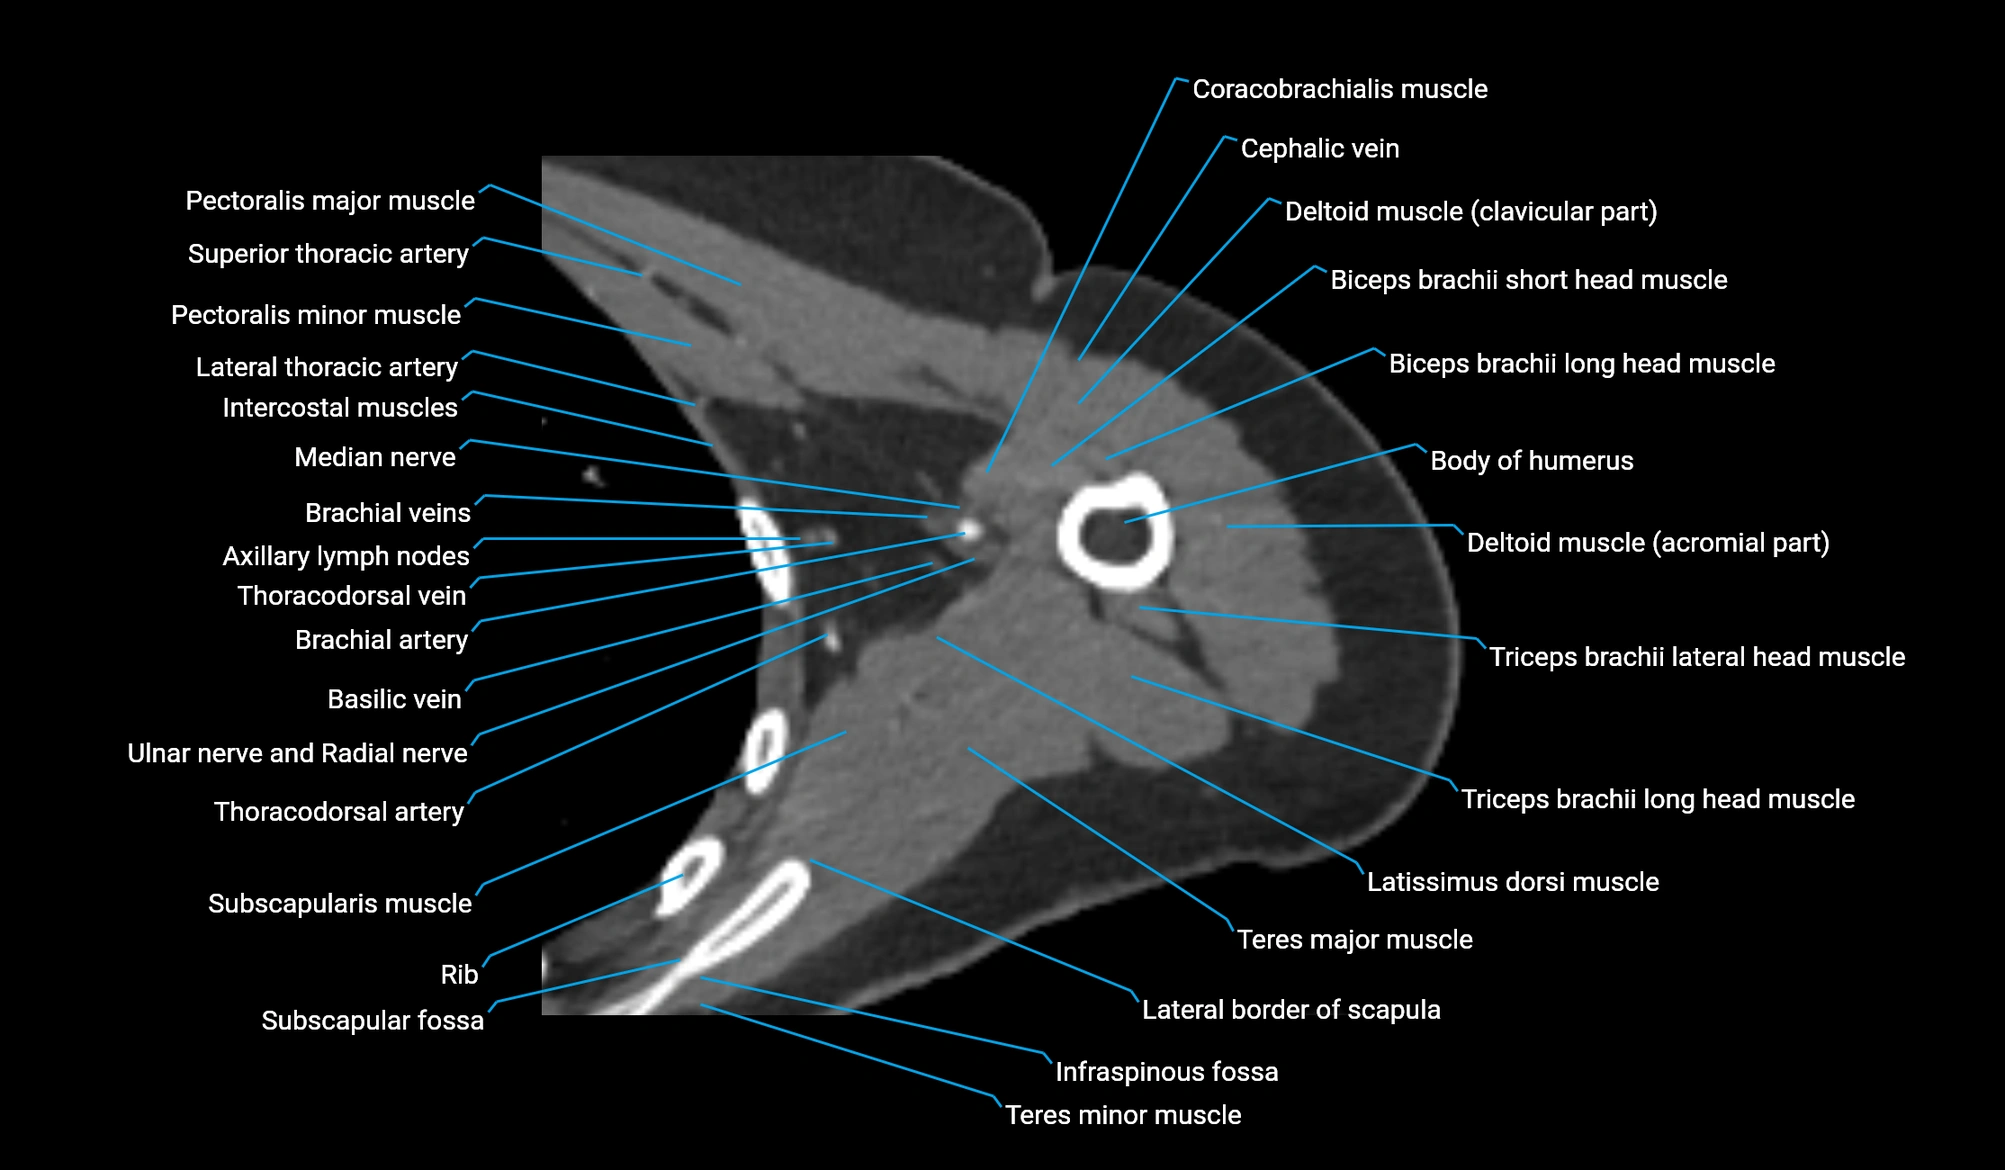

- Body of humerus

- Coracobrachialis muscle

- Cephalic vein

- Clavicular part of deltoid muscle

- Biceps brachii muscle

- Brachial artery

- Axillary lymph nodes

- Subscapularis muscle

- Teres major muscle

- Teres minor muscle

- Lateral border of scapula

- Infraspinous fossa

- Subscapular fossa

- Thoracodorsal artery

- Deep brachial artery

- Median nerve

- Radial nerve

- Ulnar nerve

- Long head of triceps brachii muscle

- Lateral head of triceps brachii muscle